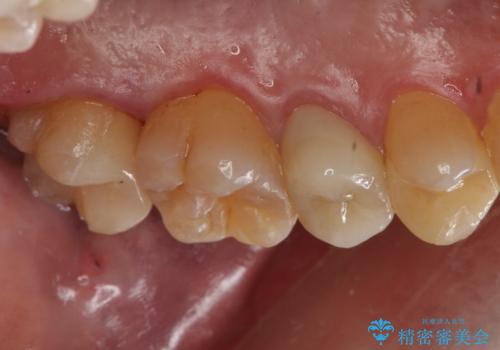

放置していた虫歯 セラミックインレーによる治療

- 右上7 セラミックインレー 77000円×1本費用は治療当時の料金となります

治療後は食事の際の痛みもなくなり、快適に過ごせているそうです。

虫歯の影響で食べ物が詰まりやすくなってしまうと、歯磨きも難しくなりさらに虫歯が大きくなっていきやすいです。